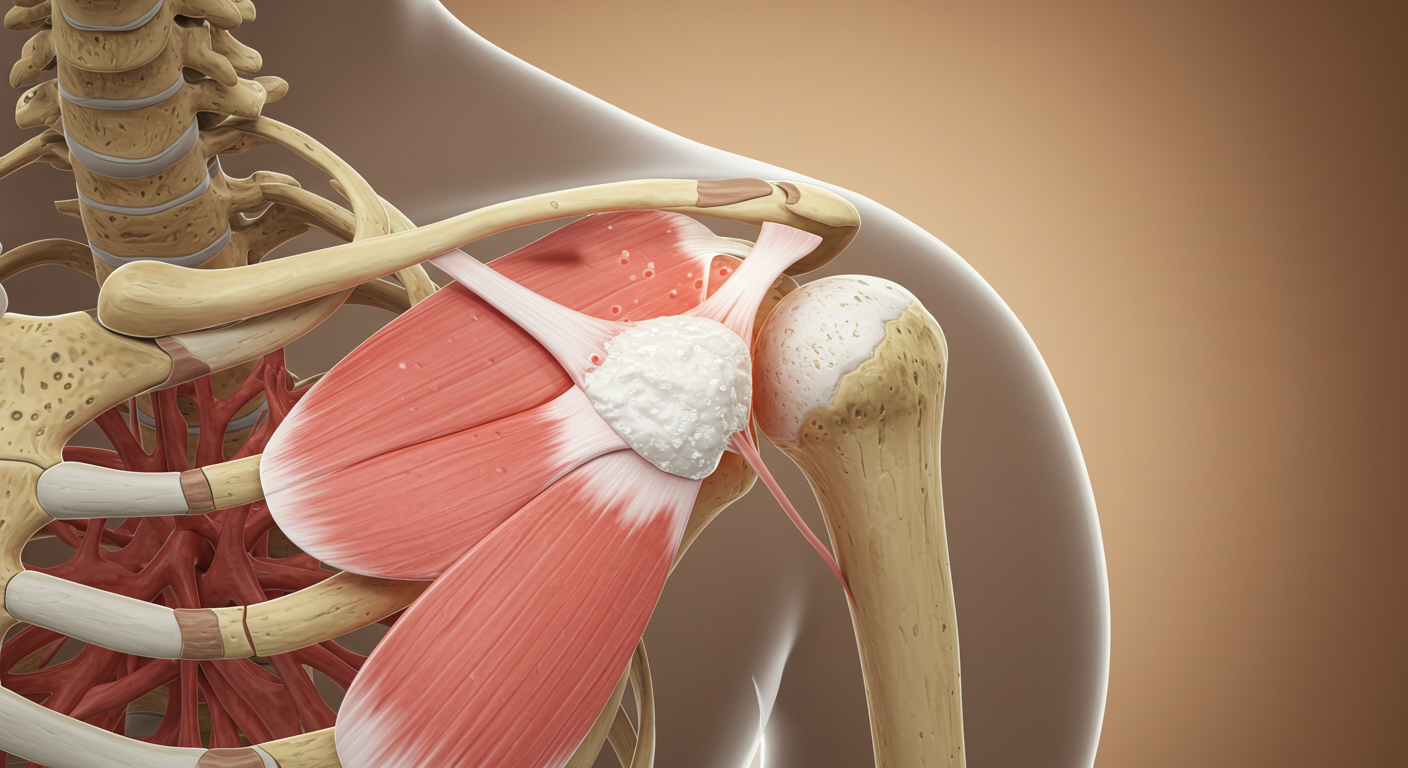

석회성 힘줄염은 말 그대로 어깨 힘줄에 석회(칼슘)가 침착되어 염증을 일으키는 질환이에요. 아직까지 정확한 원인은 밝혀지지 않았지만, 주로 힘줄의 퇴행성 변화나 미세한 손상, 혈류 감소 등이 원인으로 지목되고 있습니다. 30~50대 연령층에서 비교적 흔하게 나타나는데, 특히 어깨를 많이 사용하는 직업이나 반복적인 운동을 하는 분들에게 더 잘 생긴다고 해요. 꼭 나이가 많아야 생기는 건 아니라는 거죠.